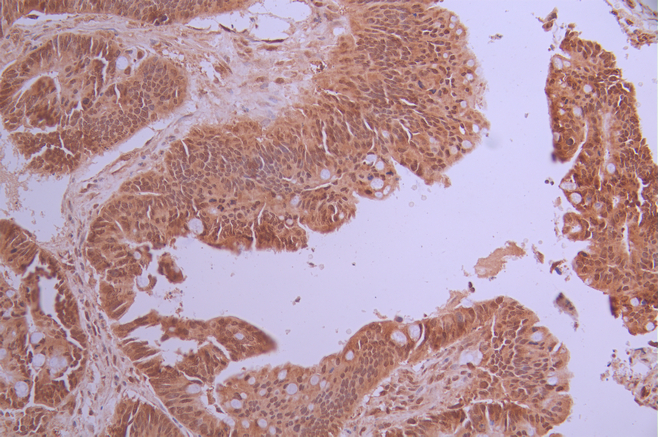

IHC image of CSB-RA056037A0HU diluted at 1:100 and staining in paraffin-embedded human colorectal cancer performed on a Leica BondTM system. After dewaxing and hydration, antigen retrieval was mediated by high pressure in a citrate buffer (pH 6.0). Section was blocked with 10% normal goat serum 30min at RT. Then primary antibody (1% BSA) was incubated at 4°C overnight. The primary is detected by a Goat anti-rabbit polymer IgG labeled by HRP and visualized using 0.05% DAB.